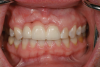

Fig 1. Badly damaged endodontically treated maxillary anterior tooth.

Figure 1

In the case presented in Figure 1 and Figure 2, the author based the decision to restore a badly compromised maxillary central incisor on his clinical experience and the patient's desire to keep the tooth, and while the restoration lasted several years, the esthetic result turned out to be poor due to the gray show-through at the gingival area and deep below the tissue from the root (Figure 2). The literature has indicated that this dark discoloration may be due to the use of certain intracanal medicaments during the root canal procedures, including some antibiotic pastes and/or liquids, or possibly the previous use of metallic restorative material in the canal.7,8 Removal of this discoloration is difficult and Zimmerli et al showed in a literature review that different bleaching techniques offer limited success and a high incidence of the discoloration returning.9